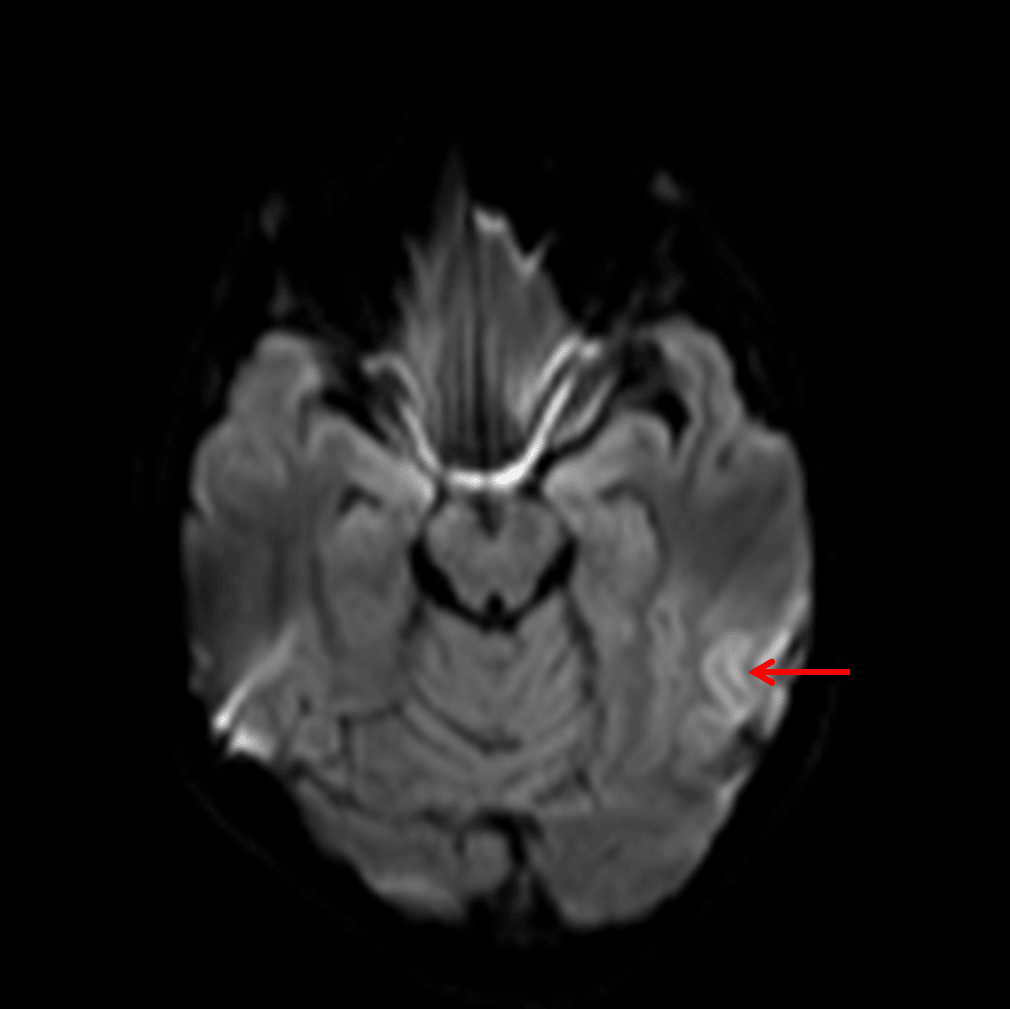

Faint cortical diffusion signal hyperintensity (red arrow).